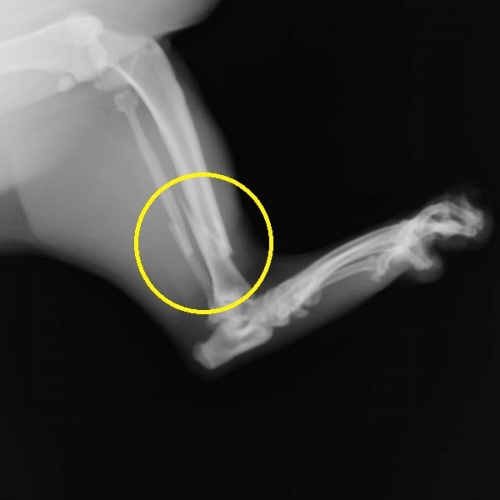

下の写真が手術後3か月目のものです。補強のためのレジンとピンの約半数を除去した後の写真です。

だいぶ身軽になったせいでしょうか、持ち前のファイターぶりにさらに拍車がかかってしまい、包帯の交換やら注射などの処置はかなり大変になりましたが、ご家庭では活発に3次元に動き回っているようです。

ここまで来ればもう大丈夫でしょうか。。。

あと一か月程度ですべての固定を除去できそうです。

レントゲン写真を撮るとこんな感じです。